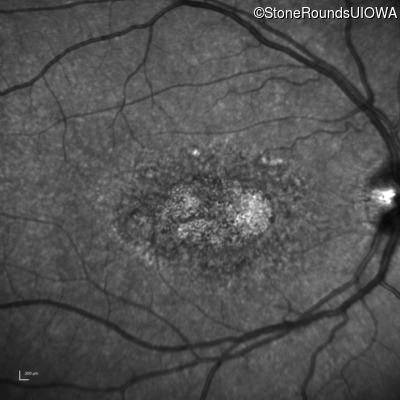

Age at visit: 29 years

This 29-year-old man had good vision until his early 20's. at which time he began to experience a slow reduction in his acuity. His driver's license was restricted at age 27.

Age at visit: 29 years (Visit 2)